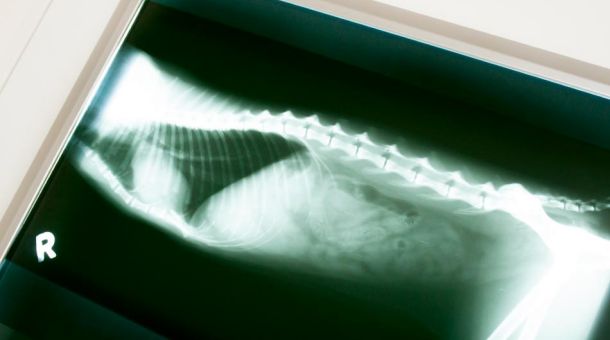

Röntgenuntersuchungen

- Weichteil-Röntgen

- Skelett-Röntgen

- Dental-Röntgen